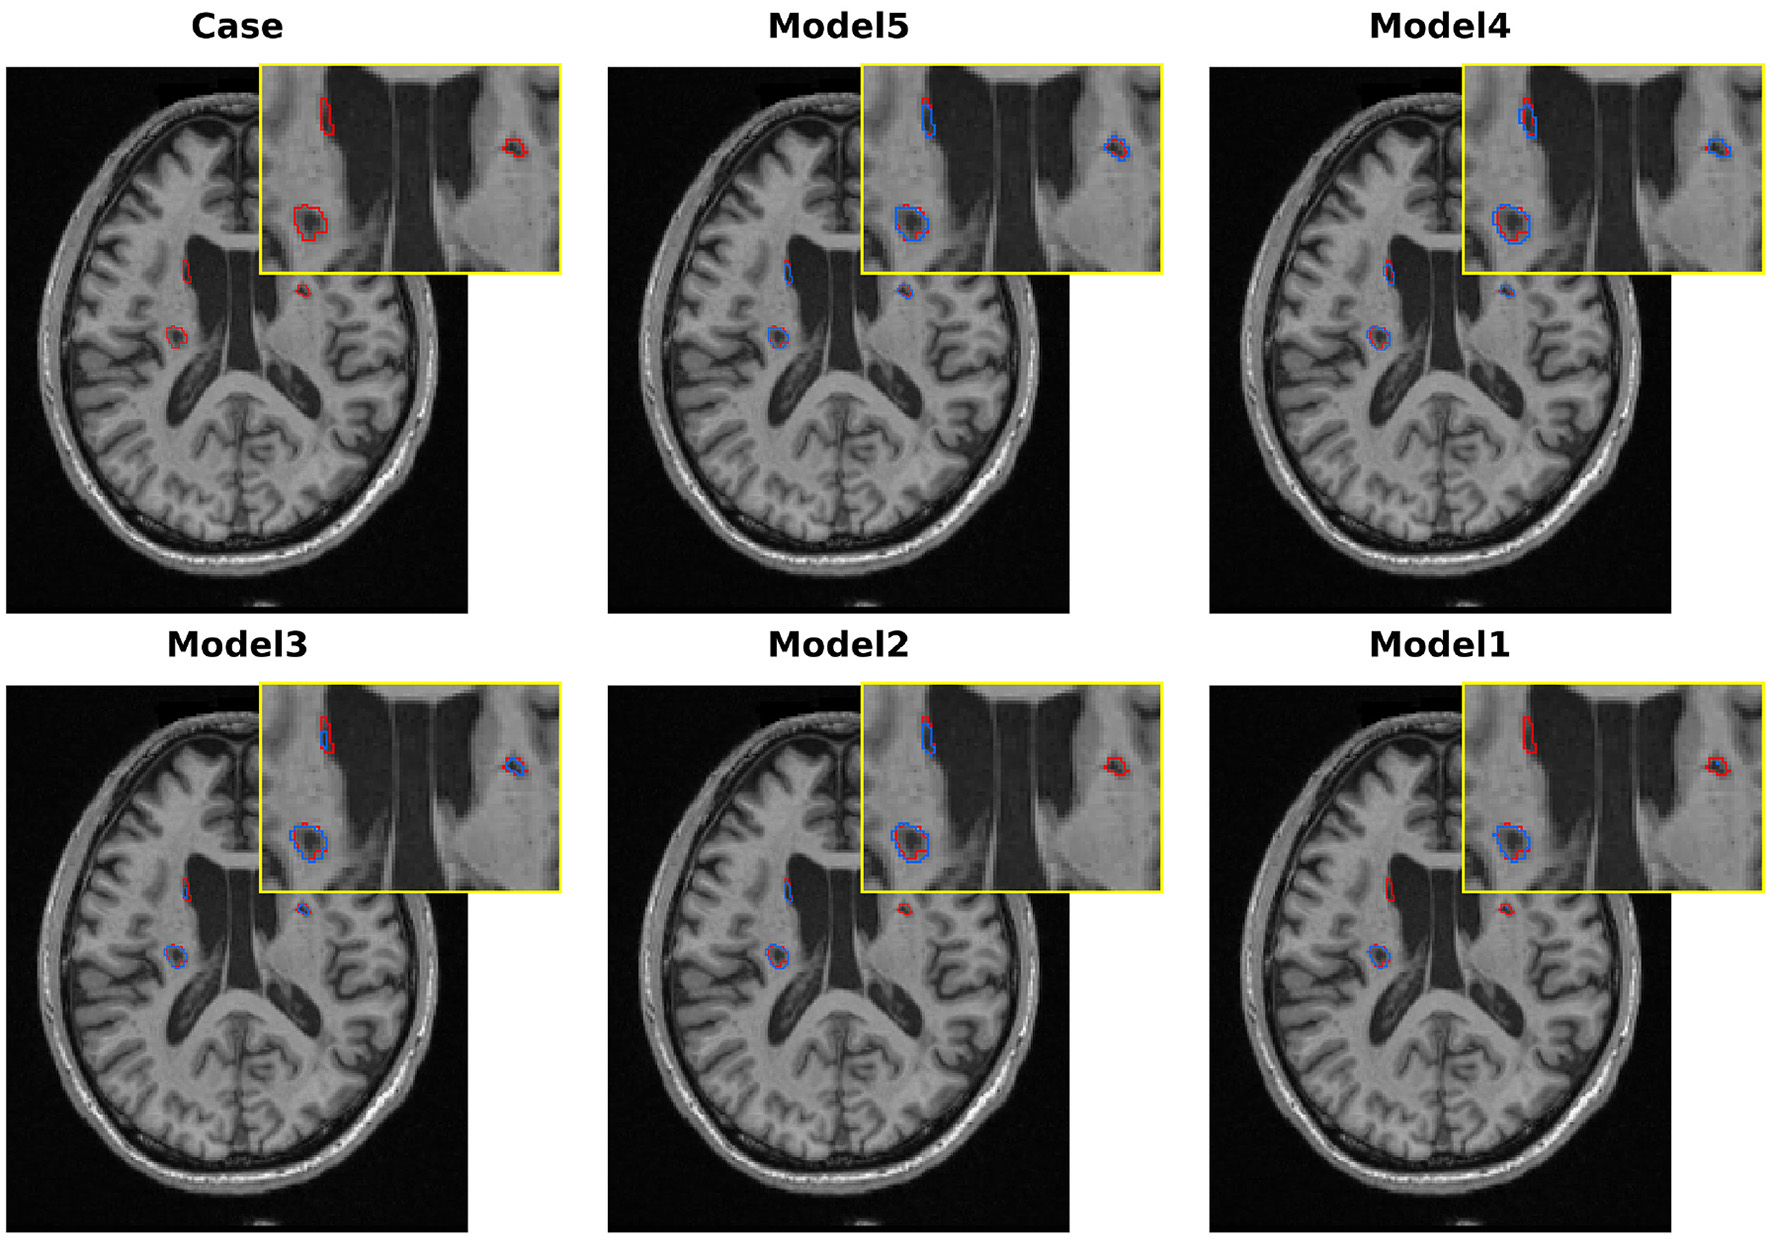

Figure 10

Qualitative comparison of various models in melting research on the ATLAS v2.0 dataset.

Our baseline model, the standard 3D U-Net, obtains Dice = 50.06% and IoU = 41.39%. As shown in Figure 10, the model can roughly locate the lesions, but it clearly undersegments them and fails to capture the complicated boundaries of the lesions. These results demonstrate the limitations of traditional convolutional networks in modeling the variety of sizes and irregular shapes of stroke lesions.

To alleviate the limitations of the baseline in multi-scale feature extraction, we replaced the conventional encoder with our proposed LSC encoder (Model 2). The single modification leads to a remarkable improvement in the Dice score (+10.03 percentage points, 60.09%). As shown in Figure 10, the qualitative results also support this improvement, where the model outlines a more complete region of the primary lesion area. These results demonstrate the effectiveness of the LSC module in learning features from various receptive fields, which are crucial for modeling both core and peripheral areas of lesions. However, the model is still unable to detect the lesions in the opposite hemisphere.

To validate the effectiveness of global context modeling, we swapped out the baseline decoder for BSC-Mamba (Model 3). With this setup, we obtained Dice score of 63.11%. From Figure 10, we can see that Model 3 was able to model bilateral lesions, which demonstrated the power of BSC-Mamba to model long-range dependencies and utilize distant spatial information. Meanwhile, the model lost its fine-grained local information and thus led to slight under-segmentation in boundary regions.

After independently validating the effectiveness of the encoder and decoder, we concatenate the encoder and decoder to build Model 4. This new model takes advantage of LSC's ability to extract multi-scale local features and BSC-Mamba's ability to integrate global–local information. The Dice coefficient achieves 65.03%. Visualization results show that the lesion region is more completely captured by Model 4, and the contour is sharper and clearer. However, directly fusing features may cause over-segmentation at blurred boundaries, which means that conflicting or redundant features are probably forwarded via skip connections.

To address the suboptimal feature fusion issue, we further developed the BAGF module to obtain the complete LBMNet (Model 5). Specifically, BAGF module adaptively chooses and fuses salient features from encoder and decoder pathways while suppressing noise and redundant information. With the further improvement of feature fusion, the final model achieves the best segmentation performance as shown in (Model 5: Dice = 67.57%, IoU = 54.97%). As shown in Figure 10, the segmentation masks generated by Model 5 are most accurate. That is, the boundaries of segmentation masks are clear and there is neither over-segmentation nor under-segmentation. The above results also demonstrate that the BAGF module plays a key role in integrating multi-scale and global representations to obtain robust and accurate segmentation results.